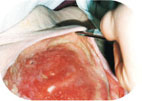

Deep wound with pockets

First, completely fill out the pocket and then wound with LIGASANO® White. Therefore cut LIGASANO® white somewhat larger piece than the wound diameter and to somewhat thicker than the wound depth. Insert it with slight compression into the wound. The purpose: complete wound contact, also at the wound edges. Generously cover the wound environment 2…